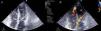

While in the coronary care unit she continued to experience malaise and faintness and her hypotension and oliguria worsened. On cardiac auscultation a grade III/VI holosystolic murmur was detected at the left sternal border, while the echocardiogram revealed akinesia of the apical segments and compensatory hypercontractility of the basal segments, with preserved global left ventricular (LV) systolic function, and a diagnosis was made of non-restrictive apical interventricular septal rupture (Figure 2). Turbulent flow was seen in the LV outflow tract, with a velocity of >4 m/s and systolic anterior motion (SAM) of the anterior leaflet of the mitral valve (Figure 3). In view of LV outflow tract obstruction associated with hypotension, it was decided to discontinue dobutamine perfusion and to administer intravenous propranolol. This resulted in symptomatic improvement and increased blood pressure, and the echocardiogram showed less turbulent and slower flow and improvement of SAM (Figure 4). It was thus possible to stabilize the patient and transfer her to a surgical center, but unfortunately she died of complications in the second week after surgery.

Quantification of dynamic gradients in the left ventricular outflow tract before (A) and after (B) discontinuation of dobutamine and administration of intravenous propranolol (1 mg/kg). The peak gradient in (A) is >64 mmHg with blood pressure of 90/60 mmHg; in (B) the peak gradient has fallen to 16 mmHg and blood pressure has risen to 110/70 mmHg.